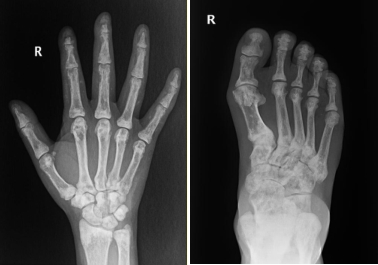

辅助检查:心电图检查示窦性心律,室性早搏。血管彩超见右上肢动脉中内膜点状钙化斑形成,左上肢动静脉内瘘血管中内膜点状钙化斑形成(图1)。双下肢和双手X线检查:双手诸骨骨质密度不均匀增高,部分远节指骨骨质吸收(图2),右手指骨周围见血管钙化影和结节状高密度影,诸小关节在位,关节间隙尚可,周围软组织未见明显肿胀;双髋关节在位,髋关节间隙变窄,双侧股骨骨质密度增高。双膝、双踝关节,双足诸小关节在位,关节间隙尚可,双膝、双踝、双足关节面下骨质密度不均匀增高(图2)。心脏彩超检查:双心房扩大,二尖瓣环钙化,二尖瓣轻度反流,三尖瓣轻-中度反流和卵圆孔未闭(房水平左向右分流)。胸腹部计算机体层成像(CT)平扫:(1)双肾萎缩钙化;(2)全身广泛骨质密度增高;(3)脾脏饱满,动脉粥样硬化。与2021年5月21日胸部X线片比较,胸廓诸骨骨质密度增高稍有进展(图3)。骨髓涂片检查:骨髓细胞增生减低,中性粒细胞系占68.0%,以分叶核细胞为主,嗜酸细胞可见;红细胞系占1.2%,成熟红细胞大小不均,部分细胞中心淡染区扩大;淋巴细胞比例增高;未见巨核细胞,血小板散在。骨髓病理检查结果:骨髓部分组织破碎,伴纤维组织增生,增生程度无法明确判断,骨髓小梁结构紊乱伴髓腔变形,部分小梁硬化,髓腔内见多量结晶样物沉积,有少量偏成熟粒细胞散在分布,未见红系和巨核系(图4A),偏振光镜下可见特征性双折射(图4B)。

注:患者双手和双足骨质密度不均匀增高,双手部分远节指骨骨质吸收

本例PH患者接受维持性血液透析治疗4年,除肾脏受累外,还伴有多系统病变,总结如下。(1)重度顽固性贫血:患者乏力明显,精神萎靡,贫血貌,在外院反复接受输血治疗,且在使用较大剂量罗沙司他情况下,血红蛋白仍波动在65 g/L左右。患者粪便潜血阴性,可排除消化道出血,结合病史、骨髓活检以及硫代硫酸钠经验性治疗效果,证实草酸盐结晶骨髓沉积是骨髓造血受损的主要病因。既往也有文献报道重度顽固性贫血是PH患者特征性表现之一。需要注意的是,本例患者以贫血为主要表现,白细胞和血小板计数正常,这与既往报道的全血细胞减少存在差异[5, 6]。经文献检索发现,本例患者骨髓组织草酸盐结晶的病理表现是目前已报道病例中最具有特征性改变的病例。(2)骨痛、骨关节畸形和骨质密度增高:患者主诉双手疼痛麻木,伴有双足跟疼痛,四肢关节活动受限。结合其胸腹部CT表现为全身广泛骨质密度增高,以及X线检查示双手诸骨骨质密度不均匀增高,部分远节指骨骨质吸收;髋关节间隙变窄;双侧股骨骨质密度增高;双膝、双踝、双足关节面下骨质密度不均匀增高,提示草酸盐沉积于骨导致骨钙化,而非一般性肾性骨病,后者常以骨质疏松、骨软化、纤维囊性骨炎及病理性骨折为特征。由于PH的罕见性和缺乏大样本的系统研究,PH骨损害的流行病学特征目前仍不清楚。值得注意的是,即使在未出现临床症状时,部分患者已出现明显骨损害影像学改变[7]。我们既往报告的1例PH 1型患者也是以骨质密度增高、骨组织破坏、骨结构紊乱,草酸钙沉积骨及骨周组织改变为临床特征[3],与本例相似。因此,早期的骨骼系统筛查可能对PH诊疗有着重要价值。(3)心脏病变:虽然目前尚无草酸盐沉积于心脏的直接证据,但本例患者血压较前显著降低,波动在80~83/54~50 mmHg,肌钙蛋白I升高;心脏彩超检查示双心房扩大、二尖瓣环钙化。心脏病变受到多种因素的影响,本例患者除考虑贫血外,还可能与草酸盐沉积于心脏组织有关。既往也有草酸盐沉积于心脏组织的文献报道[8]。(4)血管钙化:草酸盐沉积于血管是PH患者发生血管钙化的重要发病机制[9]。本例患者血管彩超结果示左右上肢动脉中内膜点状钙化斑形成;胸腹部CT亦可见较广泛血管钙化;X线检查示右手指骨周围见血管钙化影。目前,草酸盐沉积于血管的选择性仍不明确。研究显示,皮肤微血管功能障碍可作为PH 1型患者心血管损害的早期标志物[10],提示草酸盐较易沉积于微小血管。(5)低白蛋白血症:本例患者体重指数、血脂正常,透析充分性良好,自诉饮食合理,每次透析使用人血白蛋白10 g,但仍表现为顽固性低白蛋白血症,这与既往文献报道并不完全一致[11, 12],且与PH分型无关[13]。目前,PH患者发生低白蛋白血症的病因不清楚,考虑到PH是以肝脏特异性基因突变导致草酸盐产生过多为临床特征,肝脏基因突变间接引起的肝脏白蛋白合成异常可能是顽固性低白蛋白血症的原因。(6)高凝状态:本例患者平素使用大剂量抗凝药物。即使在高强度抗凝情况下,透析器中仍可见血栓形成。同时,近6个月来反复因动静脉内瘘血栓形成而导致动静脉内瘘功能不良,血D-二聚体多次较正常值升高10多倍,纤维蛋白(原)降解产物升高数倍,表明本例患者存在高凝状态和纤溶亢进。经文献检索发现,本例为PH合并高凝状态的首次报道,其发生机制仍不清楚,推测可能与转氨酶相关基因突变导致凝血因子和纤溶蛋白合成异常及草酸盐沉积引起内皮损伤有关[14]。既往有个案报道显示,肝移植能够治愈合并血栓形成倾向的PH 1型患者[15]。